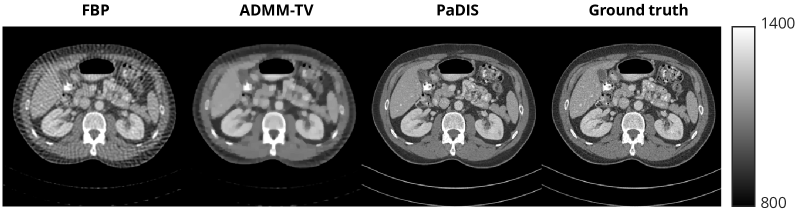

Finally, since the original AAPM dataset contained CT images of resolution 512×512512\times 512, we ran 60 view CT reconstruction experiments with these higher resolution images. Due to the lack of data, we did not train a whole-image model on these higher resolution images. We used a zero padding width of 64 and largest patch size of 64×6464\times 64 for training. Figure 8 shows the visual results of these experiments. Hence, our proposed methods can obtain high quality reconstructions for both different inverse problems and also for different image sizes.

Table 3: Results of 60 view CT reconstruction with 512×512512\times 512 images. Results are averages across all images in the test dataset. Best results are in bold.

Method FBP ADMM-TV PaDIS PSNR \uparrow 28.38 29.48 36.93 SSIM \uparrow 0.699 0.788 0.899

Refer to caption

Figure 8: Results of 60 view CT reconstruction on 512×512512\times 512 images using modified HU units.